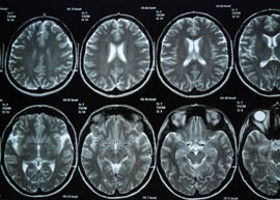

Túl sok szükségtelen képalkotó vizsgálatot írnak elő pácienseiknek az amerikai orvosok - figyelmeztettek tanulmányukban szakértők.

A Radiology című szakfolyóirat keddi számában közzétett írásában William R. Hendee, a kutatóközpontként és klinikaként is működő Wisconsini Orvostudományi Egyetem munkatársa emlékeztet arra, hogy a képalkotó eljárások túlhasználata növeli az egészségügy kiadásait, és felesleges többlet sugárzásnak teszi ki a pácienseket.

Egy tavaly év végi jelentés megállapítása szerint meghétszereződött az 1980-as évek óta az amerikaiakat orvosi diagnosztikai vizsgálatok miatt ért sugárterhelés. Az orvosi képalkotó eljárások közé tartozik a számítógépes tomográfia (CT), a mágneses rezonanciás képalkotás (MRI), a pozitron emissziós tomográfia (PET), valamint többféle szkenneléses vizsgálat.

Hendee a túl sok elvégzett vizsgálat hátterében húzódó két fő okként egyrészt utalt azokra az orvosokra, akik saját képalkotó készülékük kihasználtságát javítják ezáltal, másrészt azokra, akik az esetleges perektől védik így magukat. A szakember kiemelte a radiológusok szerepének fontosságát a vizsgálatot elrendelő orvosok tájékoztatásában és képzésében.